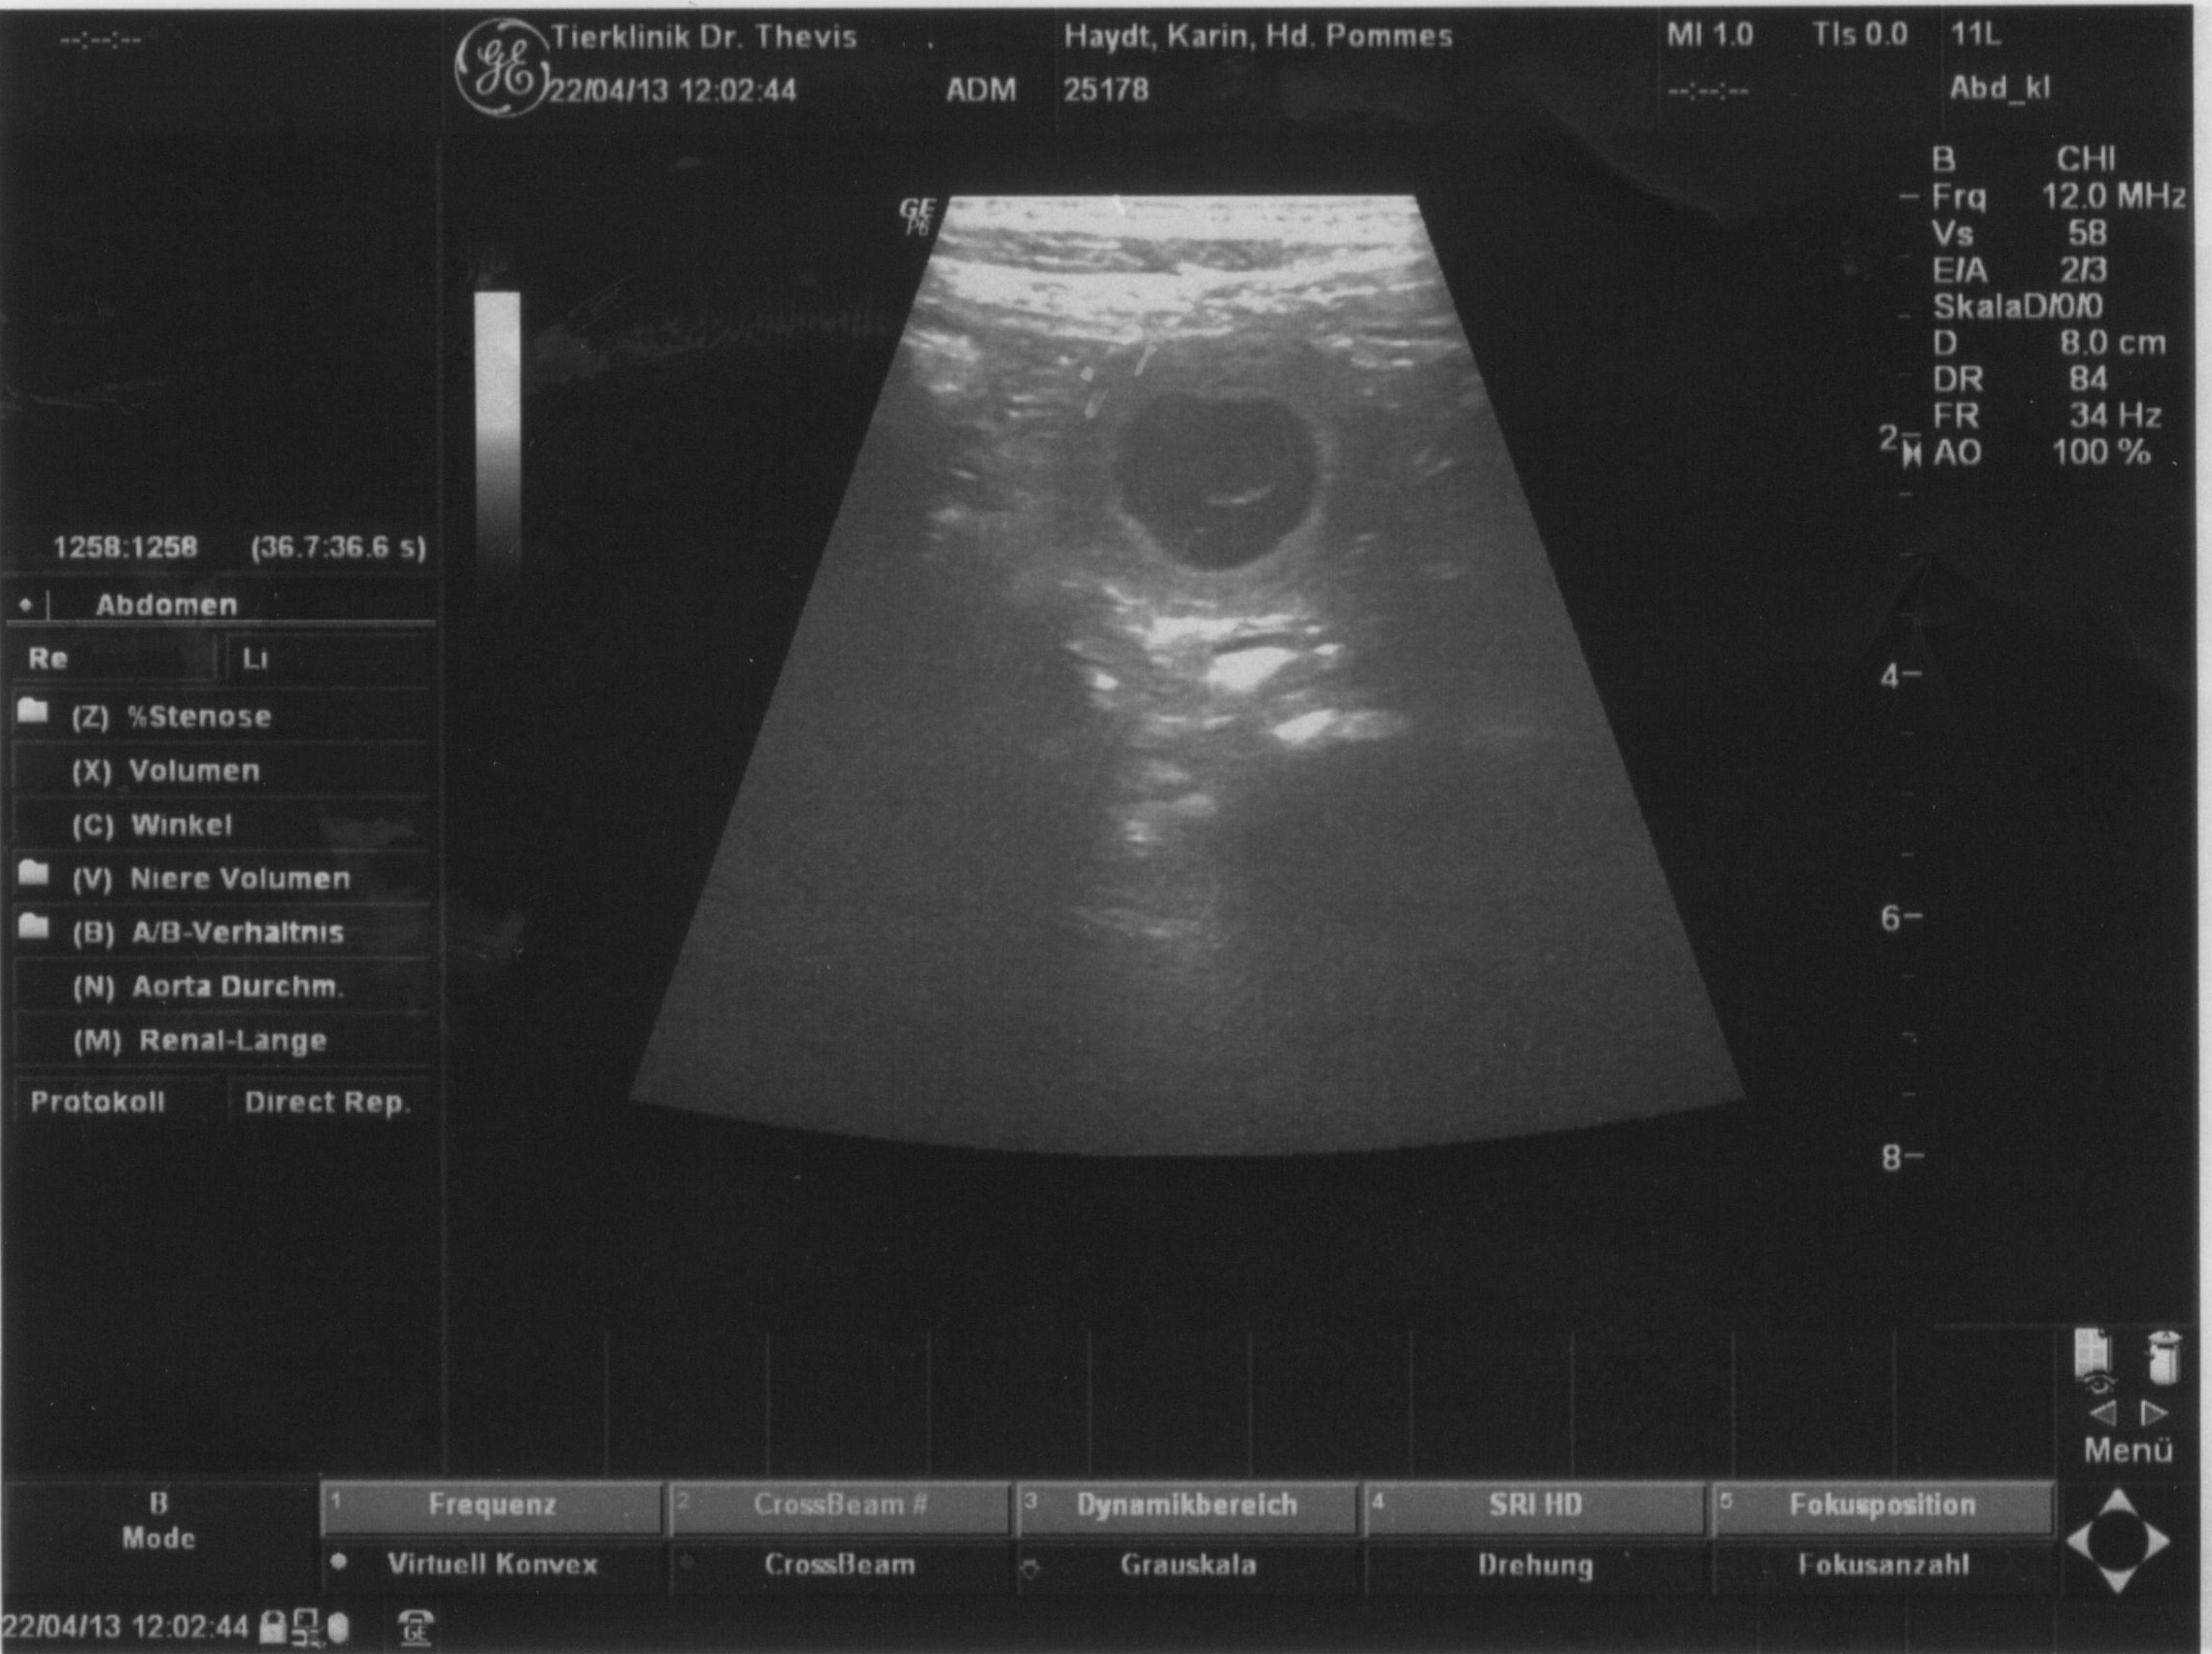

Letzte Woche waren wir beim Ultraschall und konnten mehrere Fruchtblasen erkennen.

Inzwischen kann unsere Pommes ihr süsses Geheimnis auch nicht mehr verbergen!

Wir freuen uns sehr auf die spannende Zeit, die nun vor uns liegt.